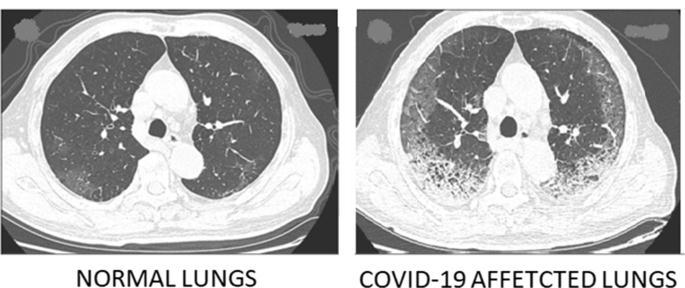

Fig.1:examplesoffrontviewchestX Rayimages.(a) NormalchestX rayimage,(b)Coronavirusinfectedchest image.

Fig.2:ViewofLungsCTScans

a)Normalx ray b)Covid19x ray